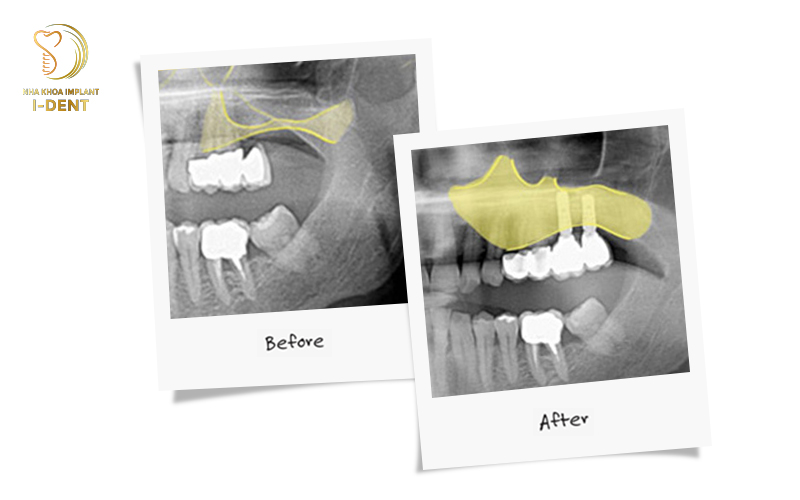

Nếu bệnh nhân mất răng hàm trên quá lâu, sẽ dẫn tới tình trạng tiêu xương hàm và xoang hàm bị thoái hóa. Khiến cho xoang hàm mở rộng và hạ xuống sát đỉnh sóng hàm trên. Lúc này, xương hàm không còn đủ chiều cao và diện tích cần thiết để đặt trụ implant. Vì vậy, để cấy ghép Implant thành công, bác sĩ sẽ chỉ định nâng xoang ghép xương trong cấy ghép Implant

Trước khi phẫu thuật cho bệnh nhân, bác sĩ luôn tiến hành chụp phim CT 3D để xác định chính xác tình trạng xương hàm. Nếu khoảng xương giữa hàm và xoang không đủ, bác sĩ sẽ chỉ định nâng xoang.